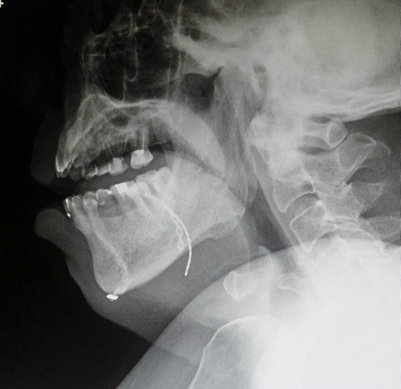

舌根钛板植入影像

舌背牵拉手术是像打舌环一样在舌背上打一条隧道,再用医用硅胶隧道管固定。隧道形成后,每晚入睡前用特制的牵引带穿过隧道挂在预制的双侧牙扣或牙套上,可有效避免舌松弛后坠阻塞咽部气道。晨起取出牵拉器,舌背上的隧道并不影响正常的说话和饮食。改良舌牵拉手术和舌背牵拉不同,鈦板植入舌内及下頜骨,用线牵拉,不用取出。

5月中旬,苏伯正式进行手术,手术过程仅仅耗时40分钟。术后第10天进行气管套管堵管,观察两天后发现苏伯睡眠呼吸顺畅,血氧正常。近日拔除气管套管,情况良好,进食吞咽顺畅、无痛感,舌活动好,言语如常。苏伯及家属喜出望外。